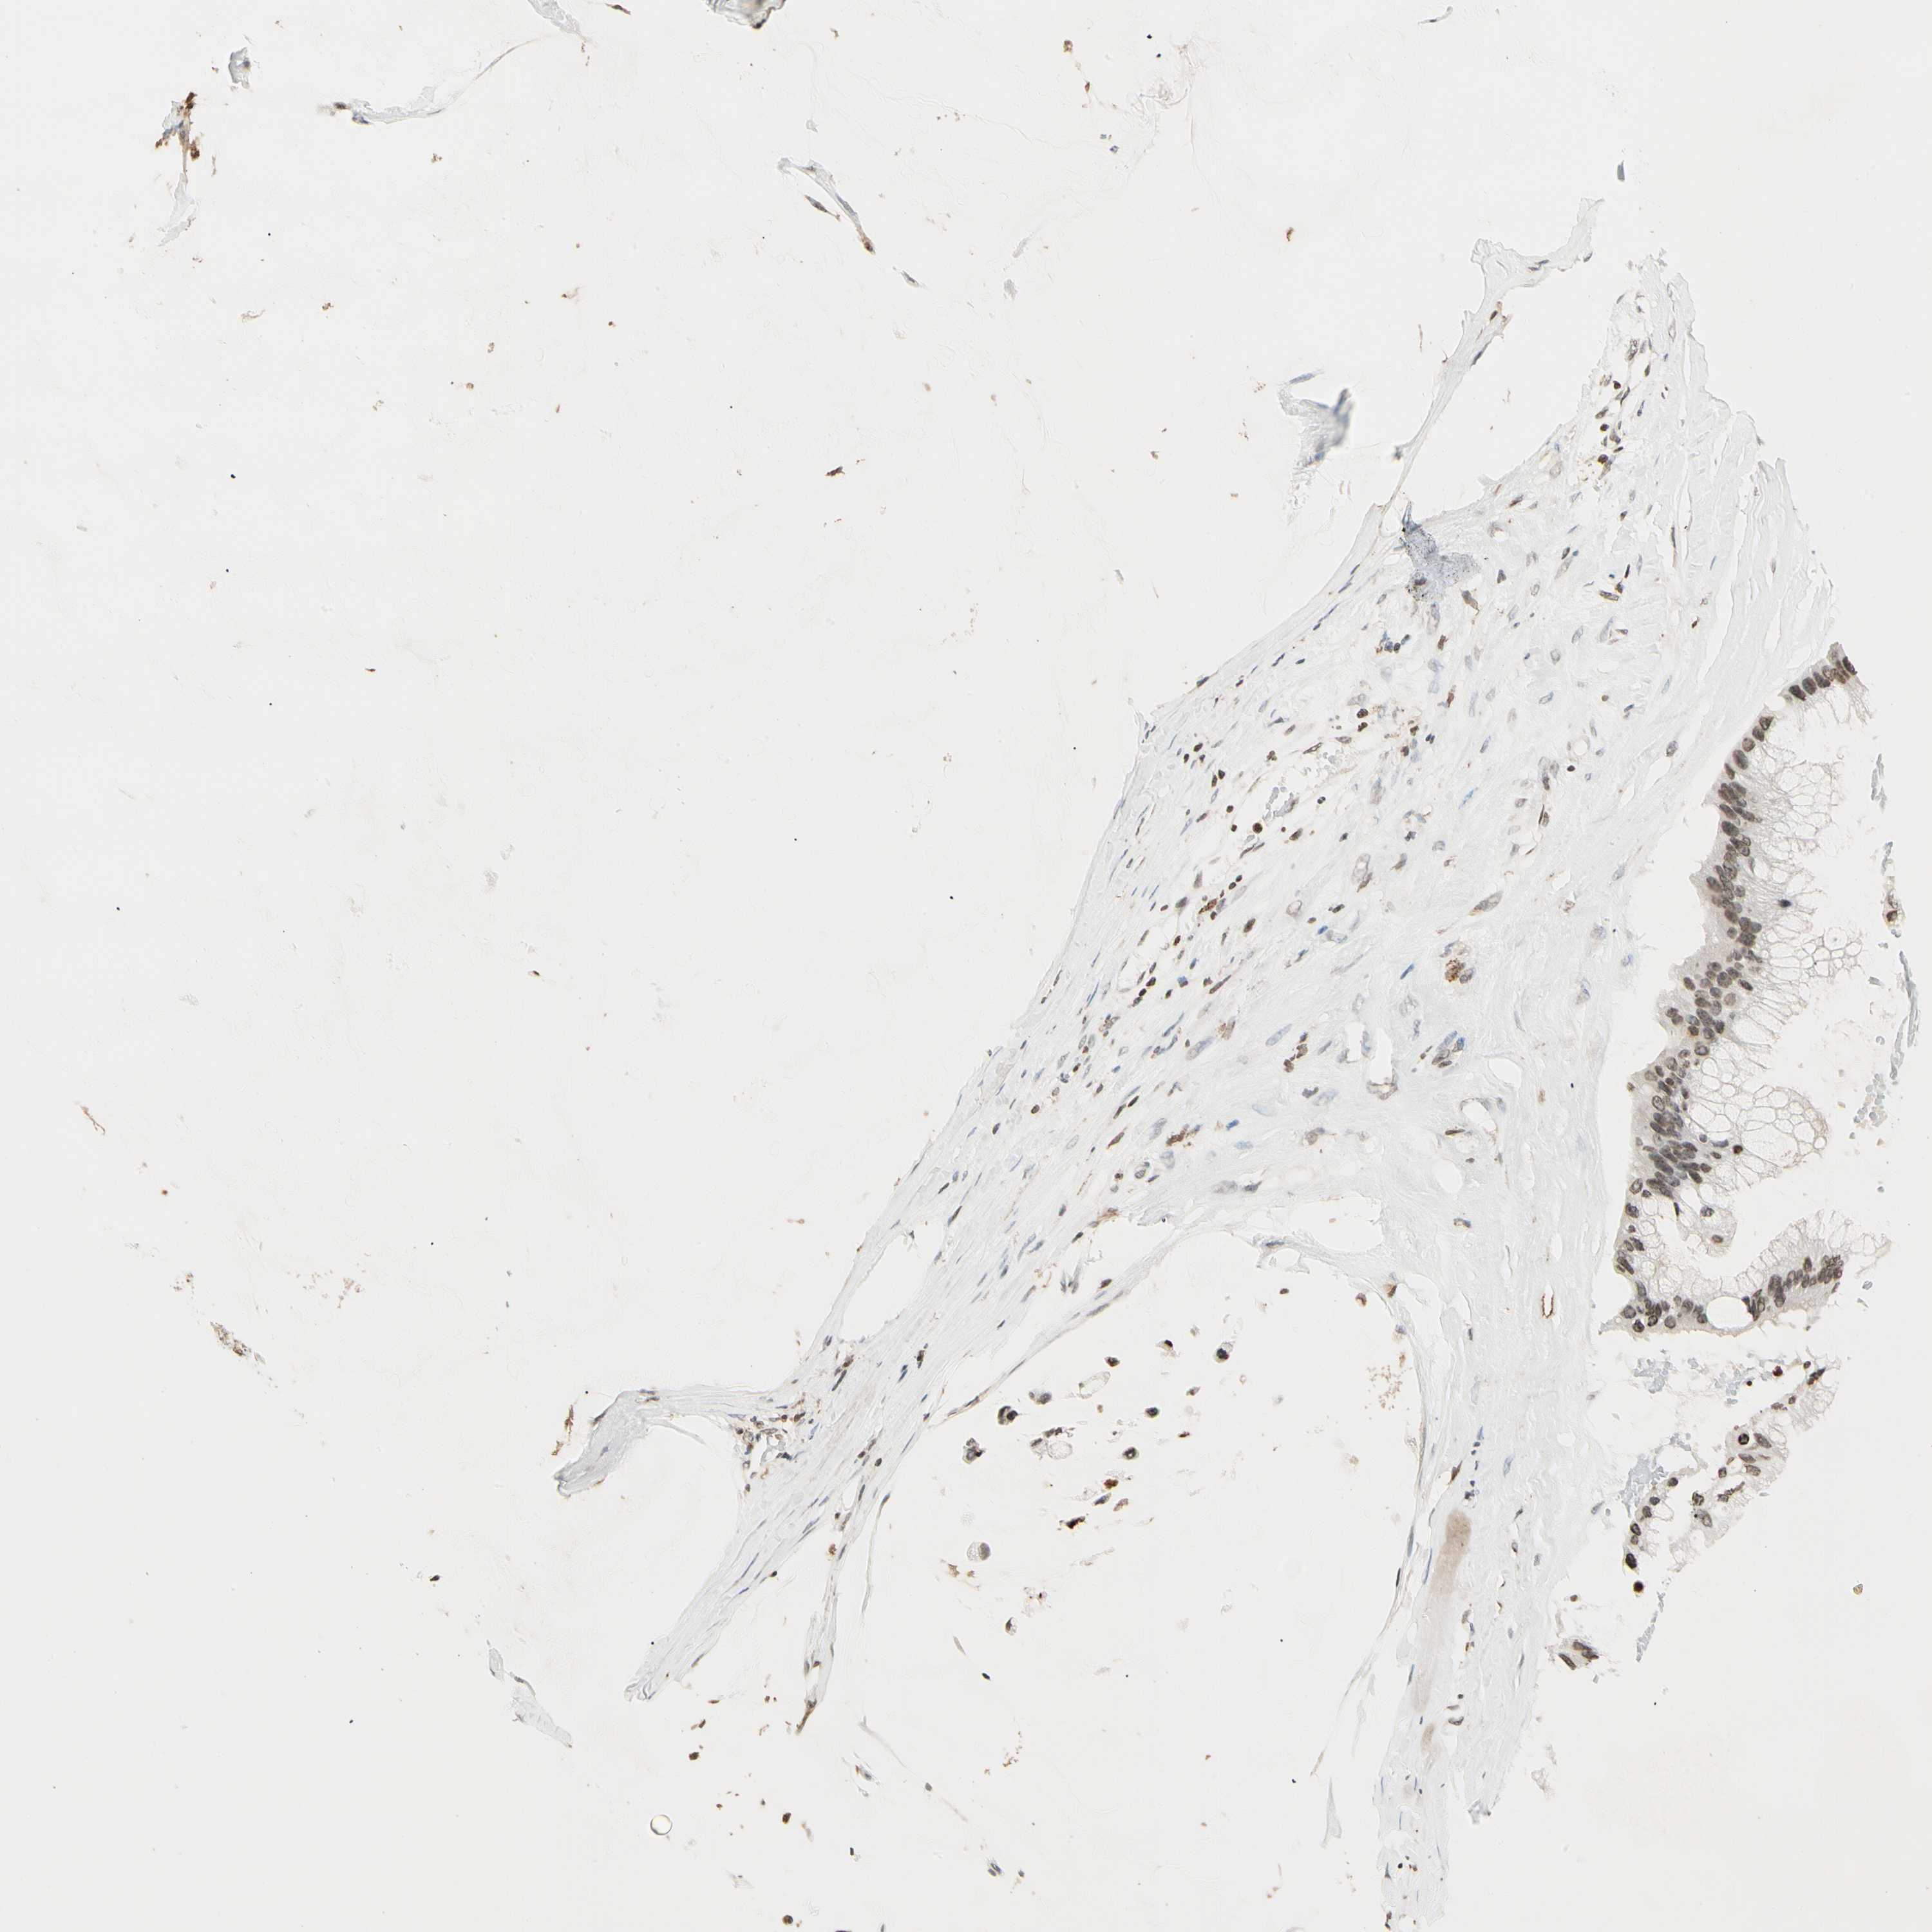

OVARIAN CANCER - Protein expressioni

A mouse-over function shows sample information and annotation data. Click on an image to view it in a full screen mode. Samples can be filtered based on level of antibody staining by selecting one or several of the following categories: high, medium, low and not detected. The assay and annotation is described here.

Note that samples used for immunohistochemistry by the Human Protein Atlas do not correspond to samples in the TCGA dataset.

Antibody stainingi

Antibody staining in the annotated cell types in the current human tissue is reported as not detected, low, medium, or high, based on conventional immunohistochemistry profiling in selected tissues. This score is based on the combination of the staining intensity and fraction of stained cells.

Each image is clickable and will lead to virtual microscopy that enables deeper exploration of all samples and also displays staining intensity scores, fraction scores and subcellular localization as well as patient and tissue information for each sample.

Antibody HPA007641

Antibody CAB022464

Staining

High

Medium

Low

Not detected

Intensity

Strong

Moderate

Weak

Negative

Quantity

>75%

75%-25%

<25%

None

Location

Nuclear

Cytoplasmic/membranous

Cytoplasmic/membranous,nuclear

Cystadenocarcinoma, serous, NOS

Carcinoma, endometroid

Cystadenocarcinoma, mucinous, NOS

Carcinoma, NOS